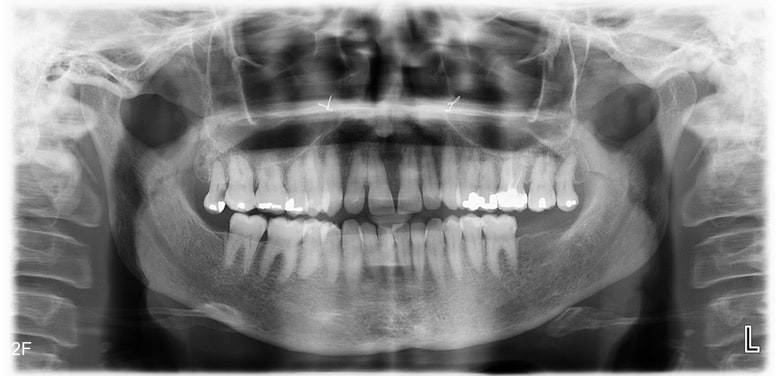

The patient had skeletal Class III tendency, skeletal and dental open bite, class I, class III dental relationship with complete open bite from 17 to 27. With constrictive maxilla the midlines were not coincident and the functional problems made the diagnosis worse.

The dental panorex confirmed a good level of bone, no periodontal problem, absence of 38, 37, 48, extrusion of 18, 28, a ceramic crown and root filing of 26 and amalgam crown filling on posterior teeth. The TMJ were also seen to be satisfactory.

The side view film with the initial cephalometric analysis confirmed the skeletal Class III and open bite discrepancies, the deficit of the upper jaw head development and a slight incisor’s proclination in relation with the tongue posture. (Table 1)

The functional assessment showed that the patient suffered a Preoperative Apnea Hypopnea Index (AHI) severity of 30 per hour. The maxillary nasal constriction might increase nasal resistance and alter the tongue posture leading to narrowing of the retroglossal airway.

Radiographs were taken before the second phase, showing a huge maxillary expansion of the palatal suture with a good root integrity, a maxillary advancement of point A in relation to SN (SNA=4,7°) but an aggravation of the skeletal open bite (Go-Gn/SN=37,5°) and occlusal plane to SN (17,5°). (Table 2)